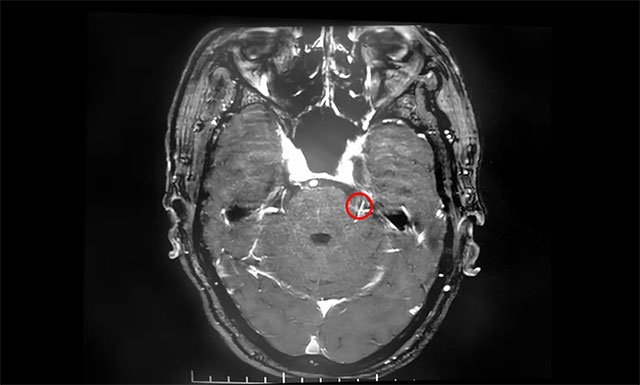

▲ 患者左侧三叉神经根部与小血管关系密切

在蔡司显微镜(双荧光)下可见,患者左侧三叉神经后根外侧有小静脉与其位置较为紧密,并可见两者间放置有垫片,考虑为前次微血管减压手术放置的垫片。沈教授小心翼翼地游离三叉神经根周围蛛网膜,灵活操作手中纤细轻巧的显微剪刀,剪断约三分之一的三叉神经后根……经过近5个小时的手术,患者生命体征平稳,安返监护室。